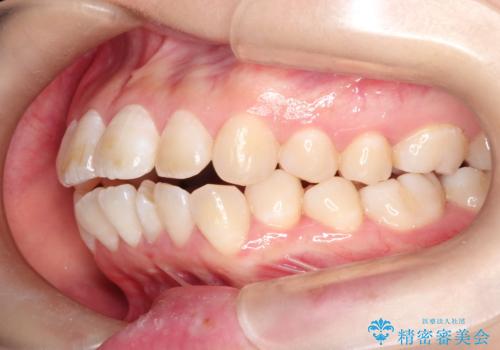

- 矯正装置

- 審美装置

- 治療計画

- ”口元を下げたい”が主訴で来院されました。

抜歯してワイヤー矯正を行い、口元も改善され大変満足していただきました。

小臼歯の抜歯を行うことで口元を改善することができました。